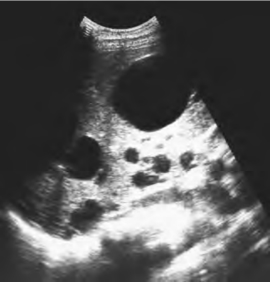

2.肝内多个大小不等、形状不一的无回声区,弥漫分布全肝,无回声区之间的肝组织回声可正常或增强,分布不均匀(图23-11)。

图23-11 多囊肝声像图

肝内多个大小不等的类圆形无回声区